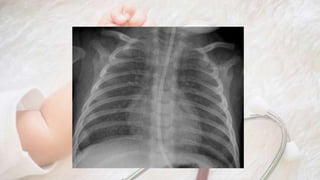

• Rx: aumento de trama hiliar, signos de atrapamiento aéreo

discreto; a veces adenopatías hiliares, atelectasias, imágenes de

peribronquitis (reiterativo)